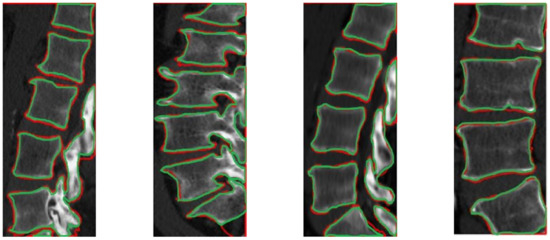

2.2. CT Segmentation for Vertebral Boundary Extraction

3.2. Results and Discussion